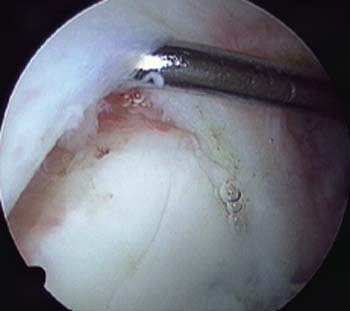

La indicación temprana de la cirugía se debe realizar en pacientes que presentan signos de compresión del nervio supraescapular secundario a ganglión en la fosa espinoglenoidea (Figura 4).47

Figura 4: Ganglión Espinoglenoideo con compresión del Nervio Supraescapular.